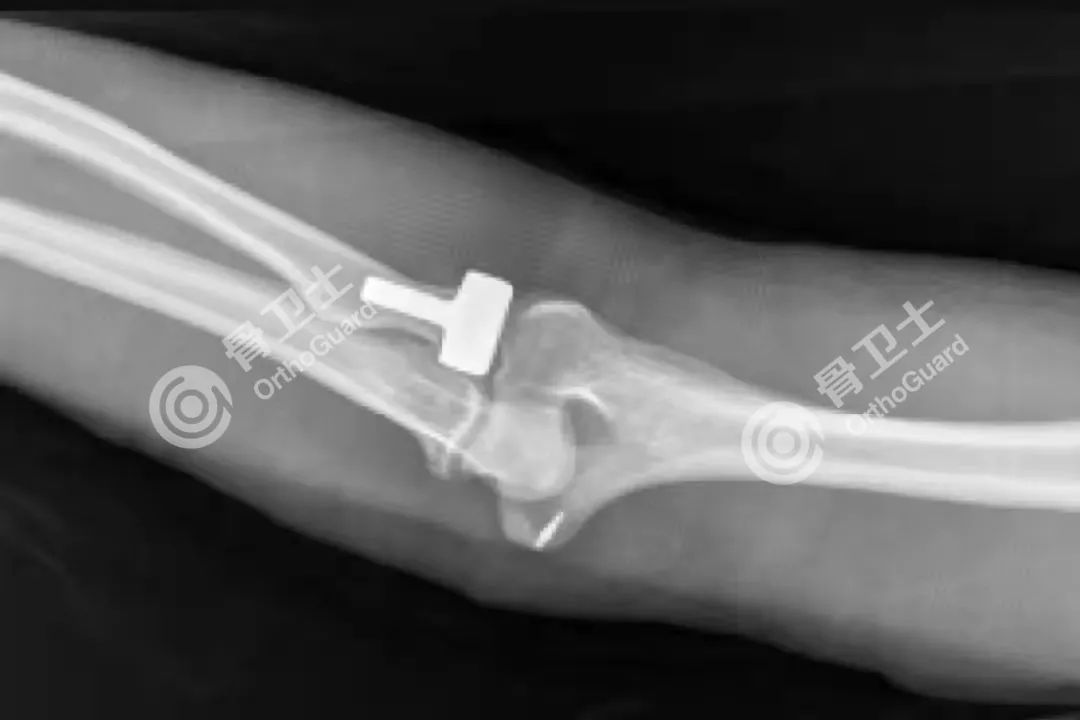

▲术后影像资料

患者经术前充分评估和准备后,骨科主任胡立冬、李锡银带领骨科团队在手术室、麻醉科的配合下,顺利完成手术。该项手术难度大,需要精细操作,一旦操作不慎,术中容易损伤桡神经,引起垂腕的并发症,手术还需要精准修补重建环状韧带,以保持肘关节稳定。术后患者病情平稳,感觉良好,各项指标正常。经过进一步治疗护理后,关节功能恢复效果满意。